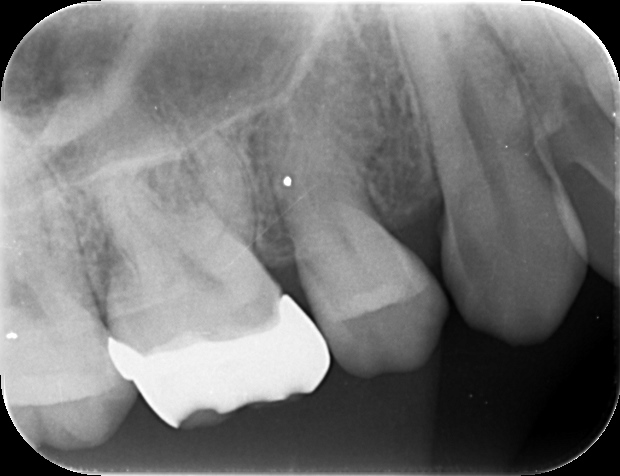

症例 上顎第一大臼歯抜髄処置 2025.10.02 【主訴】 上顎第一大臼歯部の自発痛出現にて、歯内療法専門医受診希望 【背景】 上顎第一大臼歯部に自発痛出現し、根管形態の複雑さから、歯内療法専門医にて治療を示唆 診査診断後、通報に従い、一回の処置で歯内療法及び支台歯築造まで終了し、 仮歯にて1週間ほど経過観察し、セラミック修復に至る 治療前 治療後 セラミック咬合面 セラミック頬側面 【考察】 元々、食いしばり傾向が強く認められる患者であり、メタルインレーにて咬合面をほぼ覆う形態で修復されていた この場合、咬合力コントロールされていない症例では、歯にヒビ(クラック)が生じ、噛むと痛いという訴えや、 神経に達する症状が突然出現するケースも散見される 神経が温存される症例でも、全体的にクラウン形態で修復することが望ましい 【治療回数】 歯内療法 1回 歯冠修復 2回 【治療担当医】 歯内療法 野田哲朗 歯冠修復 白土 州 この記事のタイトルとURLをコピーする